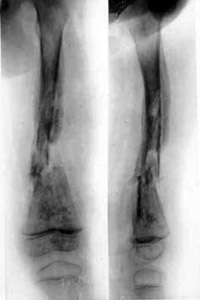

Osteomyelitis of left hip.Osteomyelitis of left hip.

Osteomyelitis of left hip.